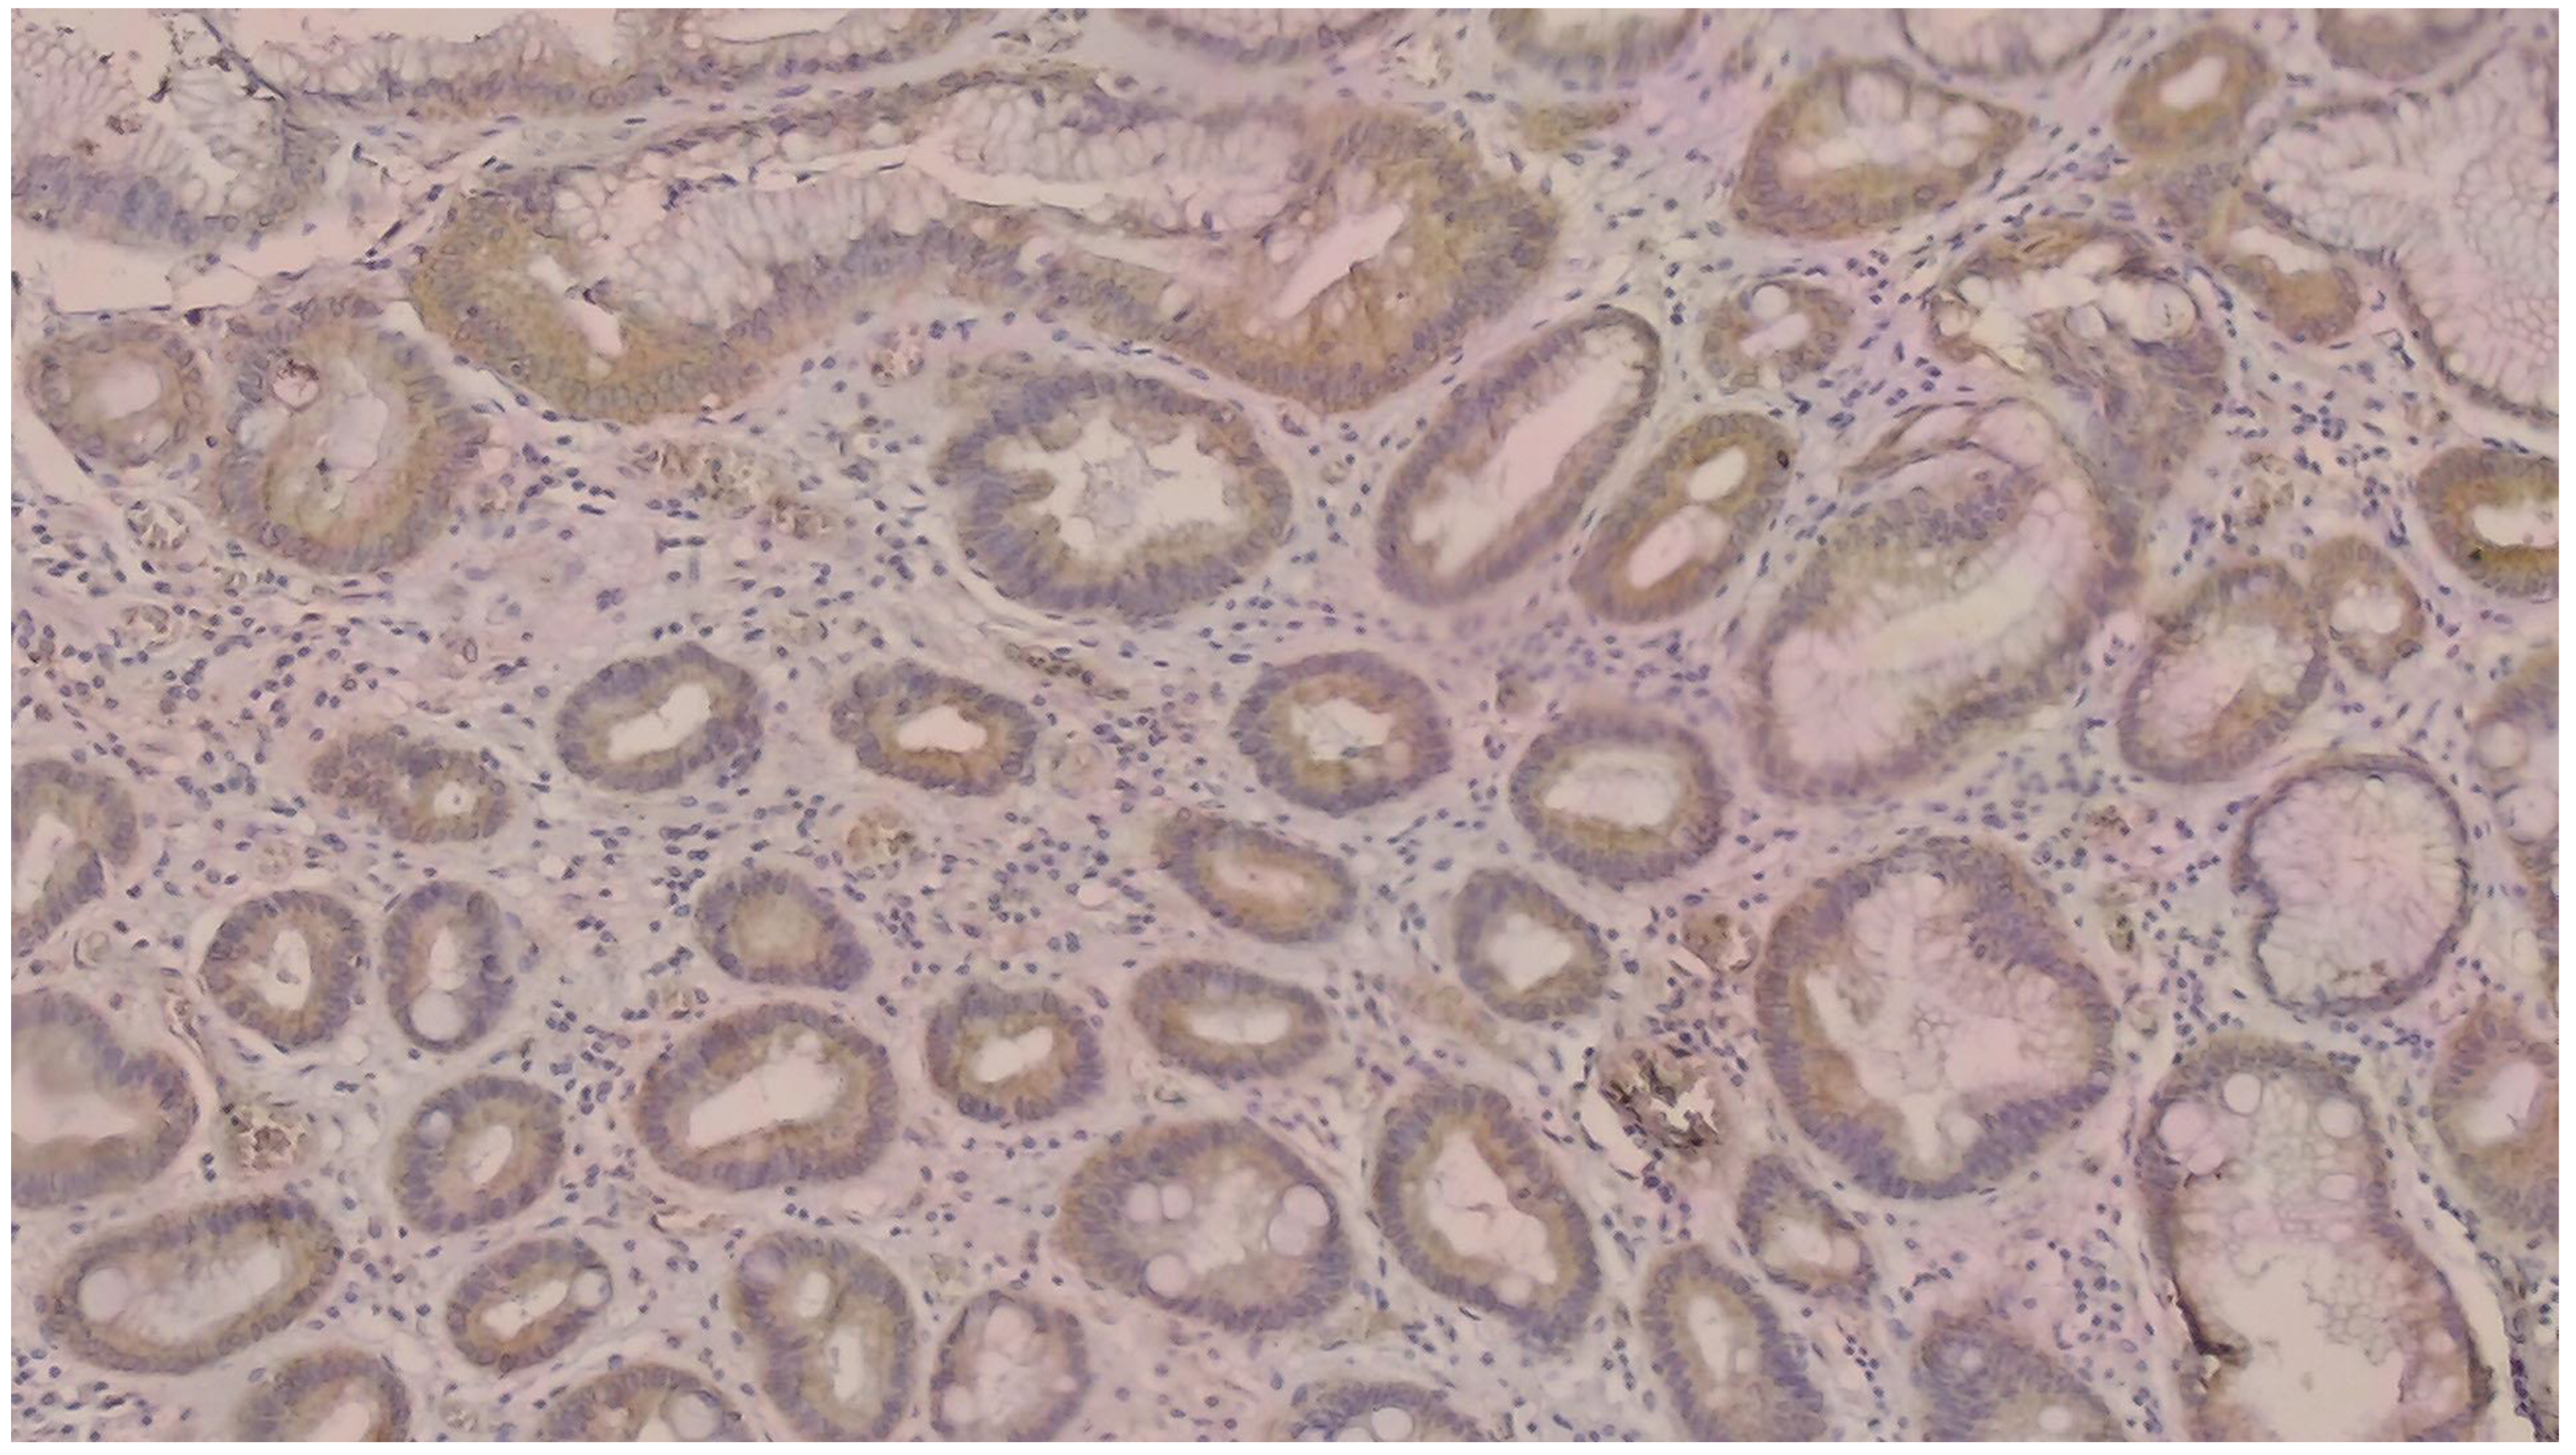

NGAL positivity was defined as diffuse or patchy areas of strong cytoplasmic and/or nuclear staining [Figure 1]. In addition, we counted the number of NGAL positive inflammatory cells that infiltrated the tumors per HPF, which was defined as NGAL positivity in the tumor microenvironment [Figure 2]. KIM-1 positivity was described as diffuse or patchy areas of strong cytoplasmic staining [Figure 3]. Since no tumors with nuclear NGAL expression alone were found, the tumors could not be grouped as nuclear and cytoplasmic expression. For both antibodies, strong focal staining or diffuse but very weak staining visible under a microscope was regarded as KIM-1 or NGAL negativity. Both antibodies were not scored because very weak staining was considered as negative.

Figure 2.

Note the NGAL-positive inflammatory cells in the tumor microenvironment (DAB × 200).